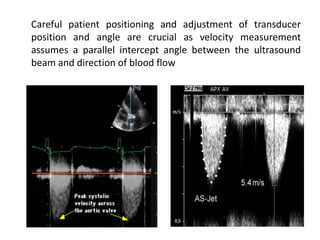

Careful patient positioning and adjustment of transducer

position and angle are crucial as velocity measurement

assumes a parallel intercept angle between the ultrasound

beam and direction of blood flow

 Apical five chamber view, suprasternal view, right

parasternal view to be used for assessment

 Rarely subcostal view, left parasternal window

 Align the doppler beam with the direction of flow of the

stenotic jet

Failure to do this – underestimation of severity

 Color doppler may be used to improve alignment

 Highest jet velocity obtained should be used for

calculation of gradient

Intercept angle

 Parallel intercept angle between direction of the jet and the

ultrasound beam.

 Cosine  = 1

 Intercept angles within 15 of parallel – will result in an error in

velocity of 5% or less

 Intercept angle of 30 - error of 30%

 This will result in even larger error in calculated pressure gradient